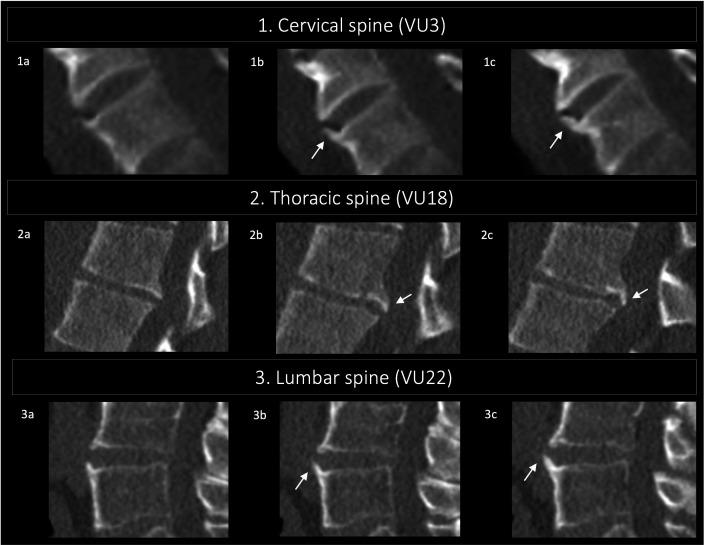

In this paper, illustrations of the different grades and views of the CTSS are presented. CTSS is used to measure bone formation in the spine of patients with axial spondyloarthritis (axSpA), in the form of syndesmophytes. In both the sagittal and coronal planes, syndesmophytes can be graded from 0 to 3 over 23 vertebral units starting at C2 and ending at S1. The CTSS ranges from 0 (absence of axSpA-related syndesmophytes) to 552 (total ankylosis of the spine).

The current atlas contains low-dose CT images of the spine without lesions (for reference) and all grades of syndesmophytes in different planes used in the CTSS. Examples are arranged per spinal segment (cervical, thoracic and lumbar).

本文展示了不同 CTSS 分级和视图的图像。CTSS 用于测量 axSpA 患者脊柱中的骨形成情况,以骨桥的形式表现。在矢状面和冠状面,从 C2 到 S1 的 23 个椎体单元上,骨桥可从 0 级到 3 级进行分级。CTSS 的范围从 0(无 axSpA 相关的骨桥)到 552(脊柱完全强直)。

目前的图谱包含无病变的脊柱低剂量 CT 图像(供参考),以及 CTSS 中不同平面的所有骨桥分级。示例按脊柱节段(颈椎、胸椎和腰椎)排列。